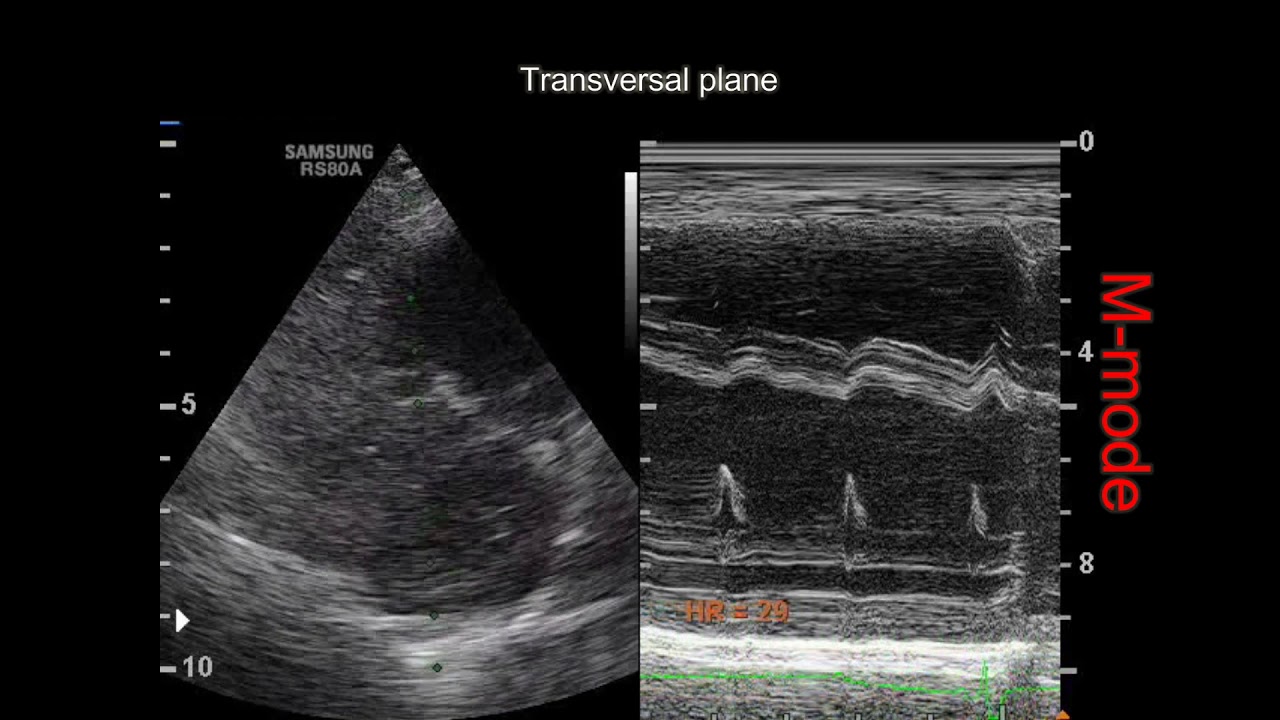

From www.youtube.com

3rd degree heart block in a dog YouTube Heart Block In Dogs  Atrioventricular block (av block) occurs when electrical impulses do not travel normally from their origin in the upper chambers of the heart. Like sinus arrest it is usually. It may not be an abnormal finding but usually is a significant problem. This interruption can happen because of a benign process, with no significance to your dog’s health. Heart block in. Heart Block In Dogs.